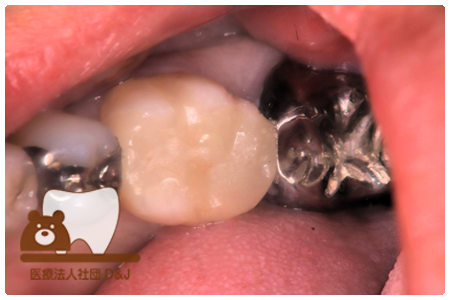

症例7フルジルコニアクラウン

治療前

治療後

43歳 女性

- 治療内容

- 虫歯で大きく失われた歯に対して、土台としてファイバーコアを使用し、その上にフルジルコニア製の被せ物を装着しました。見た目と強度を両立した自由診療の治療です。

- 治療期間

- 5カ月

- 費用

- 自費

フルジルコニアクラウン:77,000円(税込)(R7.12月現在)

- その他の治療の費用は含まれておりません。

- リスク・副作用

- 硬い素材のため、かみ合う歯に負担がかかることがあります。将来取り外す場合に歯に負担がかかることがあります。強い力が加わると、まれに欠けたり割れたりすることがあります。